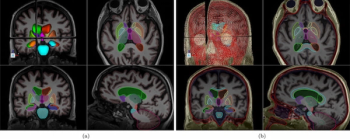

Offering rapid automated segmentation of brain structures, the ClearPoint 2.2 software reportedly enhances visualization for a variety of targeted, MRI-guided procedures.